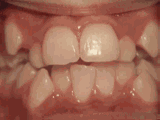

Protruding teeth, anterior teeth protrusion, and certain teeth rotation. After a professional assessment, extraction of one tooth on each side of the upper and lower jaws, followed by orthodontic treatment, resulted in the transformation shown here.